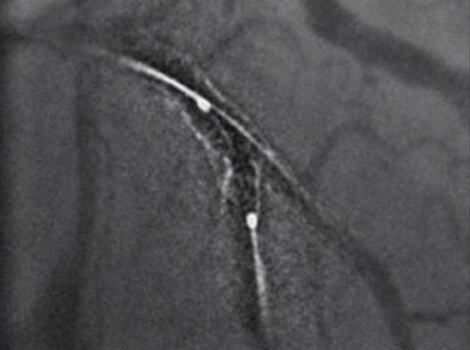

PCI ASSIST13

Help plan, assess and guide interventional procedures with improved visibility up to 85 percent in moving anatomy.

PCI ASSIST6